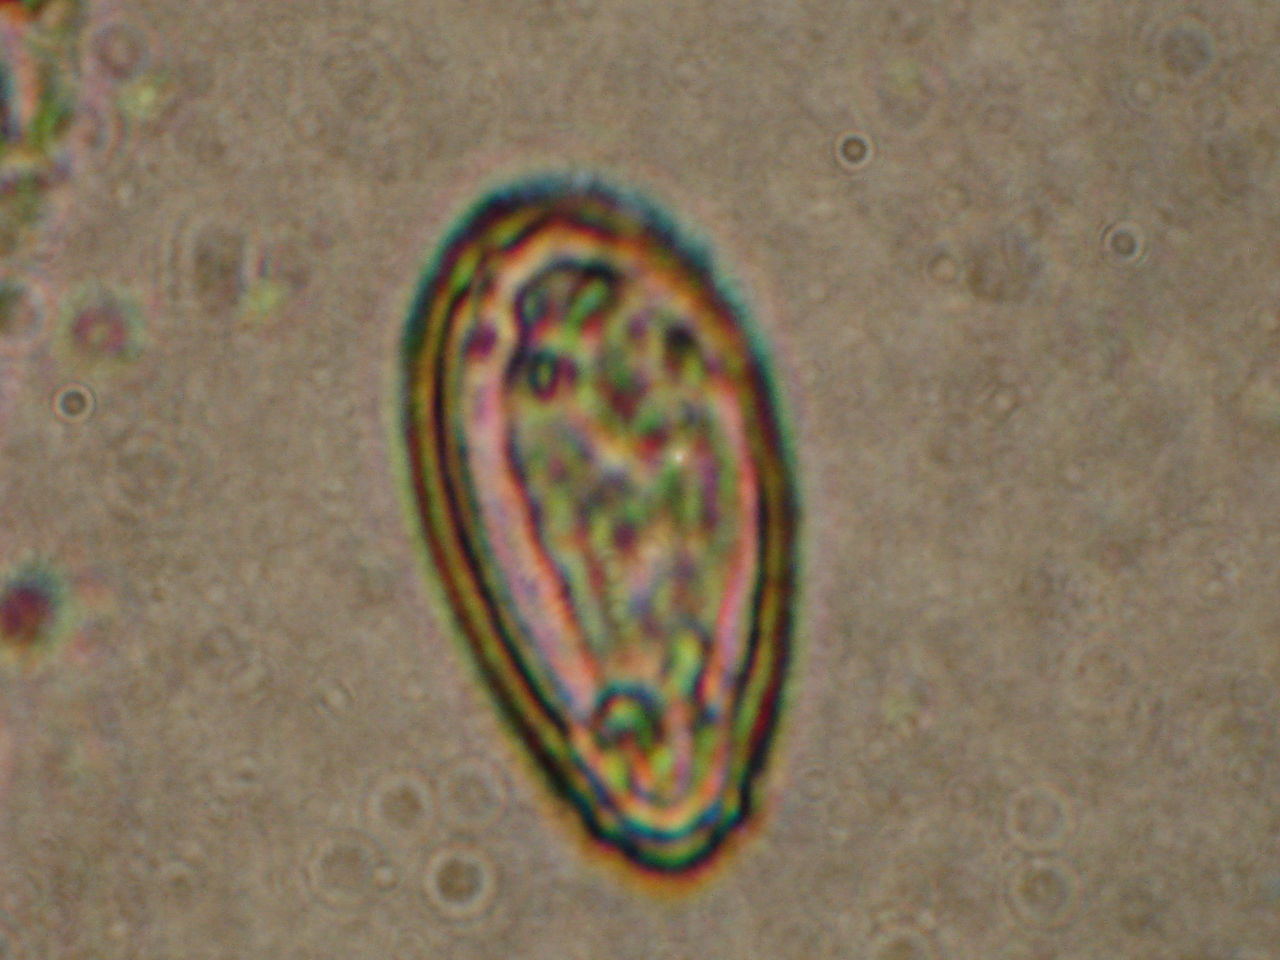

如图所示华支睾吸虫虫卵的特征

图片尺寸524x394